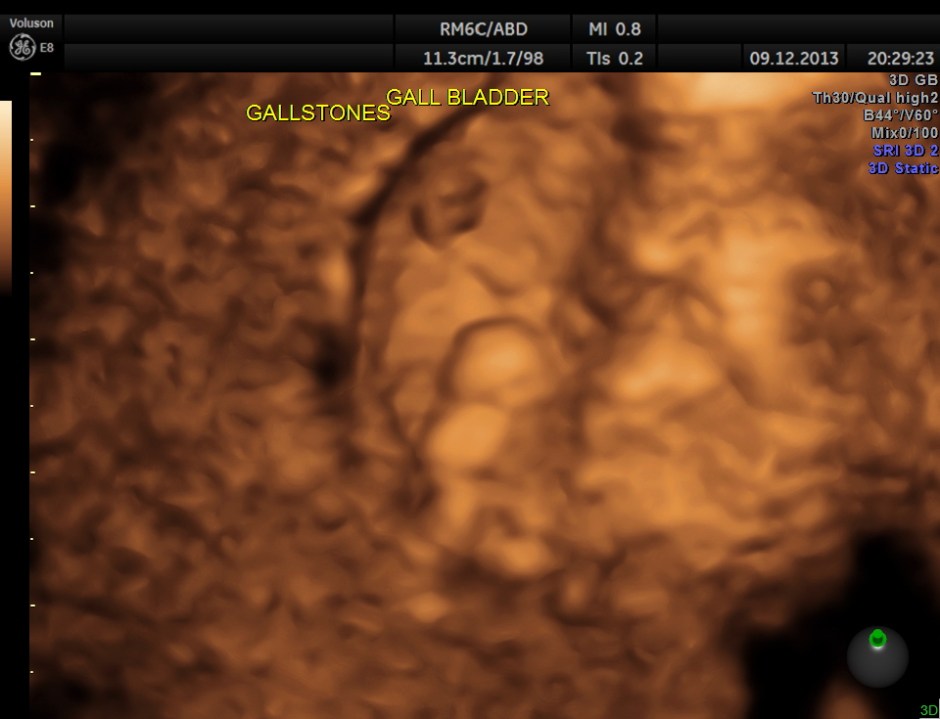

high-definition rendering is given below.

Usually the patient and the surgeon are interested in knowing the number of gallstones . I always have felt that the number would not matter . But is there a difference between 2D , 3D and more advanced high-definition rendering ? Please decide for yourself.